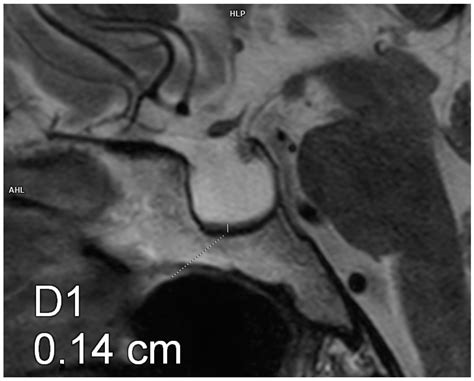

• Imaging Studies: Magnetic Resonance Imaging (MRI) is the gold standard for visualizing the pituitary gland and the sella turcica. It can show the extent of the empty sella and any associated abnormalities.

• partial empty sella mri

• partial empty sella radiology

• partial empty sella mri brain

• partial empty sella turcica